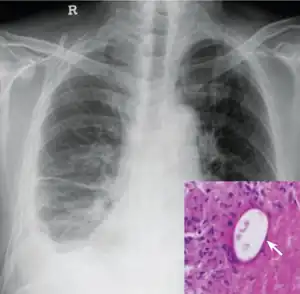

Infection

Symptoms of paragonimiasis may include abdominal pain, diarrhea, fever, and hives. If the infection remains untreated, the symptoms may diminish or disappear after only few months, but sometimes they last for decades.[6] Paragonimiasis is caused by the body's natural immune response to the worms and eggs that are present and also migrating from the intestines to the lungs.

As a rule, the parasites begin to cause symptoms about three weeks after ingesting live metacercariae. After about eight weeks, they begin to produce eggs in the lungs. Some patients develop brain damage if parasites establish in the brain and produce eggs. The brain damage commonly causes headache, vomiting, and seizures.[4] Untreated cerebral paragonimaisis commonly results in death from increased intracranial pressure.